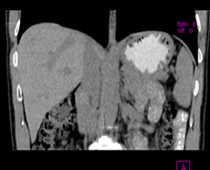

患者,男,57,常年不吃午饭,近一个月来腹部隐痛,无明显黄疸,明天进行增强扫描,图象另上传,麻烦各位帮忙一起看看讨论讨论

肝外胆管扩张,胰头增大,肠系膜上静脉似有包埋征象。

考虑:胰头占位性病变,建议增强进一步检查。

肝外胆管稍扩张,胰腺钩突略增大,但外形尚可,境界清楚。(常年不吃午饭)提示胰腺炎可能大,肿瘤第二步考虑。

支持考胰头占位性病变,感觉十二指肠壁不规则增厚,不排除十二指肠降部占位可炎症

单纯性胆总管扩张,下端梗阻.